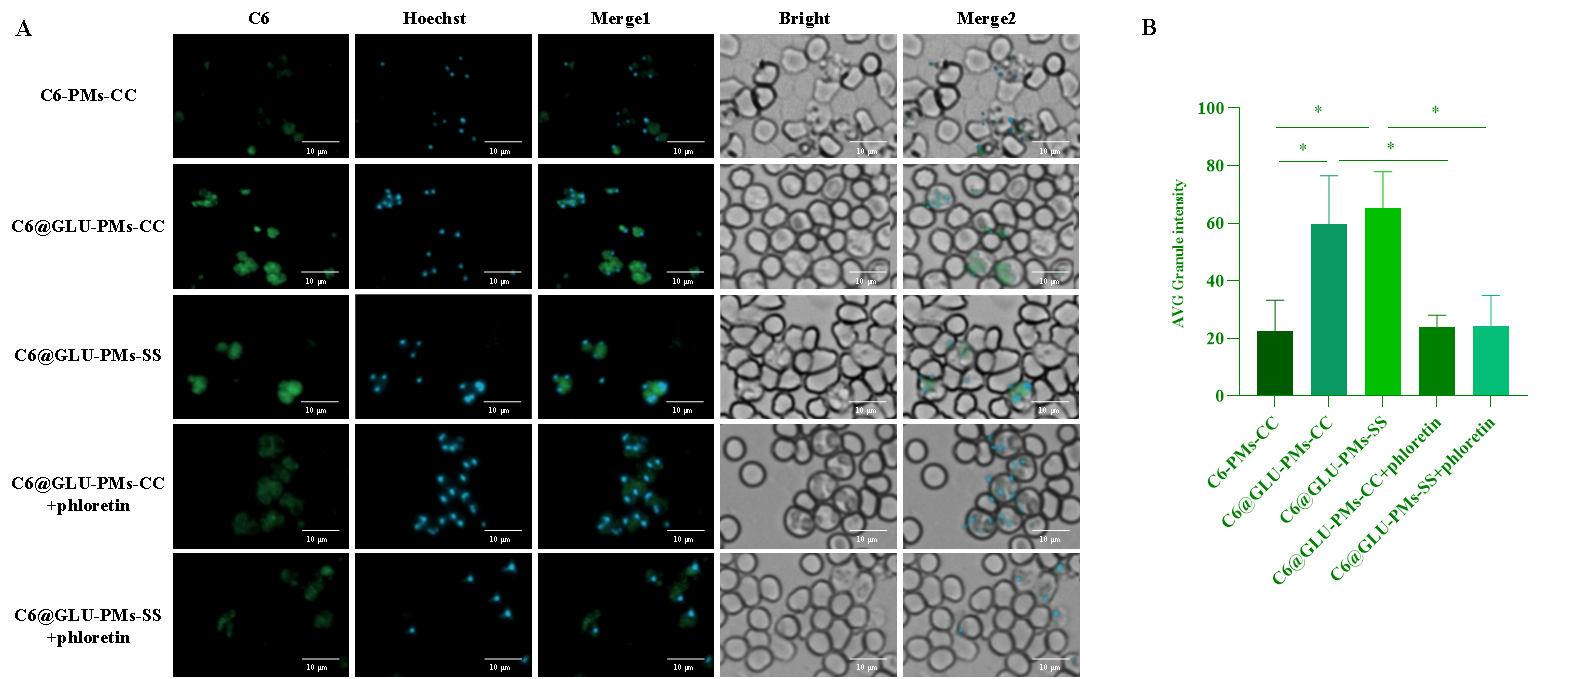

圖2 C6-PMs-CC、C6@GLU-PMs-CC和C6@GLU-PMs-SS的體外靶向性(A、B)和紅細胞內靶向性(C)評價(n = 3)

以香豆素6(C6)標記的無葡萄糖基修飾的非還原響應微粒(C6-PMs-CC)為對照,微粒與感染的紅細胞共孵育后,葡萄糖基修飾微粒在瘧原蟲中的富集顯著增強(P<0.05)(圖2)。